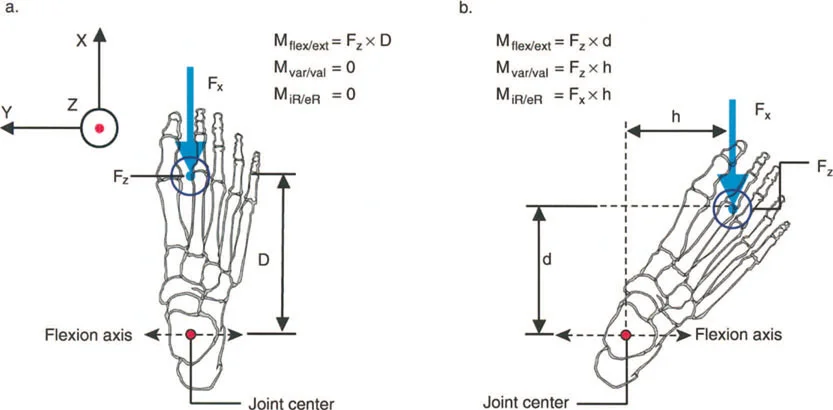

التشوهات الديناميكية هي اختلالات وظيفية تتأثر بموقع المفصل في الفراغ، ووظيفة العضلات، والأهم من ذلك، الطول الفعلي والتوجيه المكاني لأذرع الرافعة الهيكلية أثناء الحركة. على عكس التشوهات الثابتة التي تكون موجودة بغض النظر عن الحركة، فإن التشوهات الديناميكية تظهر بوضوح أو تتفاقم عندما يحاول المريض أداء حركة معينة، مثل المشي أو الوقوف.

أمثلة أخرى رئيسية للتشوهات الديناميكية تشمل "الورم الفخذي المفرط" (Severe Femoral Anteversion) و "الورك الأفحج" (Coxa Vara). في كلتا هاتين الشذوذات المعمارية، يتم تقصير الطول الفيزيائي لذراع الرافعة لعضلات المبعدة (Abductor muscles) بشكل مرضي بسبب التشوه العظمي نفسه. قد تكون عضلة الألوية الوسطى (Gluteus Medius) صحية تمامًا، ومعصبة جيدًا، وقادرة على توليد قوة بيولوجية طبيعية، لكنها تعاني من خلل وظيفي سريري عميق لأن ميزتها الميكانيكية قد سُلبت بسبب الهندسة الهيكلية المتغيرة. هذه الفئة الفرعية المحددة من الأمراض تُعرف باسم "تشوه في طول ذراع الرافعة".

يشير خلل وظيفة الذراع الرافعة إلى التغيير المرضي في علاقات الرافعة الطبيعية بين ثلاثة مكونات حاسمة:

بشكل خاص، يصف خلل وظيفة الذراع الرافعة حالة سريرية تتشوه فيها أذرع الرافعة الداخلية و/أو الخارجية بسبب سوء محاذاة العظام، أو التشوهات الالتوائية، أو تيبسات المفاصل الموضعية.

بمجرد أن يبدأ الجراح في التفكير من حيث "العزوم" التي تولد القوة، بدلاً من مجرد انقباض عضلي معزول، فإنه يبدأ تلقائيًا في فحص النصف الآخر من المعادلة الميكانيكية: الرافعة نفسها.